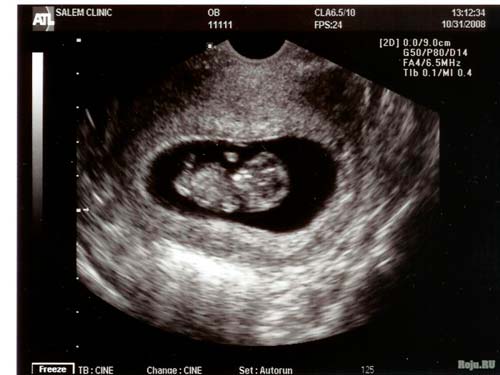

L'échographie planifiée est rarement réalisée à 10 semaines. Mais si, pour une raison quelconque, une étude est prévue, c'est l'occasion de regarder votre «magicien». Selon l'équipement et la position du petit corps, vous pouvez voir une tache blanche oblongue sur un fond sombre ou même le contour de votre propre petit homme.

Je me souviens très bien de cette semaine, car j'ai fait la première échographie et, même si beaucoup de temps s'est écoulé, je me souviens que la taille du fœtus était de 31 mm. De tous les signes de grossesse, il y avait des nausées et des vomissements très sévères et un assombrissement de la peau près des mamelons.